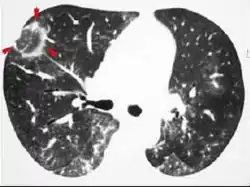

CT scan showing cryptogenic organizing pneumonia (biopsy-proven)

The reversed halo sign is seen in about 20% of individuals with COP.[17]

The chest x-ray is distinctive with features that appear similar to an extensive pneumonia, with both lungs showing widespread white patches. The white patches may seem to migrate from one area of the lung to another as the disease persists or progresses. Computed tomography (CT) may be used to confirm the diagnosis. Often the findings are typical enough to allow the doctor to make a diagnosis without ordering additional tests.[18] To confirm the diagnosis, a doctor may perform a lung biopsy using a bronchoscope. Many times, a larger specimen is needed and must be removed surgically.

Plain chest radiography shows normal lung volumes, with characteristic patchy unilateral or bilateral consolidation. Small nodular opacities occur in up to 50% of patients and large nodules in 15%. On high resolution computed tomography, airspace consolidation with air bronchograms is present in more than 90% of patients, often with a lower zone predominance. A subpleural or peribronchiolar distribution is noted in up to 50% of patients. Ground glass appearance or hazy opacities associated with the consolidation are detected in most patients.